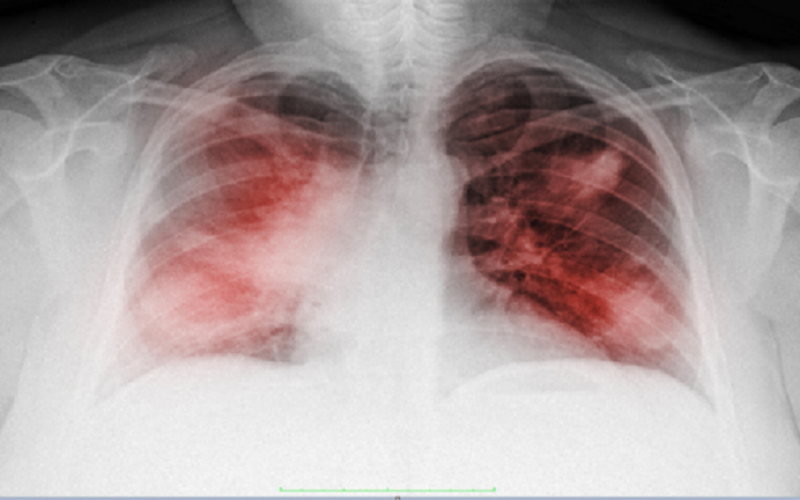

وقال، تشمل المضاعفات الصعبة، التهابا رئويا ثنائي الجانب (يلاحظ في 75% من الحالات)، ومتلازمة الضائقة التنفسية الحادة (17%) و متلازمة خلل وظيفة الأعضاء المتعدد (11%).